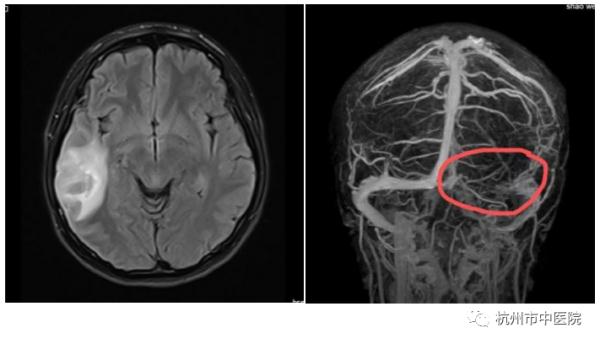

眼前这位邵女士才26岁,门诊医生仔细询问了既往史,发现患者没有什么基础疾病,或许是因近期工作压力太大或者不规律作息引起的,但出于安全考虑还是让她做了头颅核磁共振。然而报告却显示患者的左侧颞叶、枕叶不均匀异常信号,考虑急性期血肿可能,同时左侧乙状窦、横窦部也有不均匀的高信号。

患者有口服避孕药病史,加上凝血功能D-二聚体水平偏高,再结合磁共振检查结果,方芳主任考虑患者可能是颅内静脉窦血栓形成,随后立马给她安排了颅脑磁共振静脉血管成像MRV检查,果不其然在患者脑部发现了窦汇、左侧横窦及乙状窦栓塞(血栓),也就是颅内静脉窦血栓。神经内科医生给邵女士进行了低分子肝素及华法林抗凝治疗,经治疗后患者好转出院。